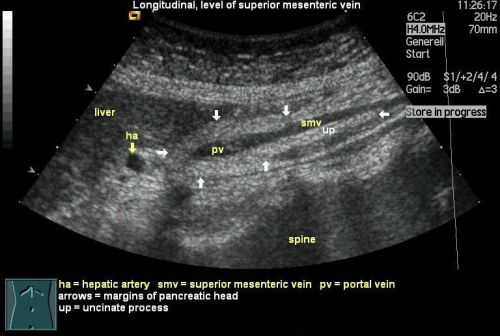

Кроме этого, врач изучает состояние сосудов, располагающихся внутри органа и возле него, что позволяет дать оценку кровоснабжения железы. В случае, если при исследовании поджелудочной железы на УЗИ были выявлены какие-либо отклонения от нормы, врачом проводятся различия между аномалиями железы. Перед ним стоит нелегкая задача отличить воспаление от опухоли, возрастные изменения в органе от хронического панкреатита и т.д.

Поджелудочная железа на УЗИ